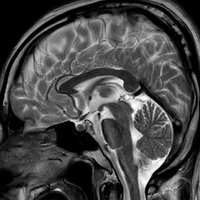

脳検査の結果が返ってきました【頭部MRI、MRA、頚部MRA】

脳検査の結果が返ってきました。 結果は・・・。